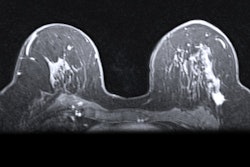

- Women with genetics-based increased risk (including BRCA1 carriers), those with a calculated lifetime risk of 20% or more, and those exposed to chest radiation at a young age are recommended to have MRI surveillance starting at ages 25 to 30. These women should start annual mammography at ages 25 to 40, depending on type of risk.

- Women diagnosed with breast cancer prior to age 50 or with a personal history of breast cancer and dense breasts should have annual supplemental breast MRI.